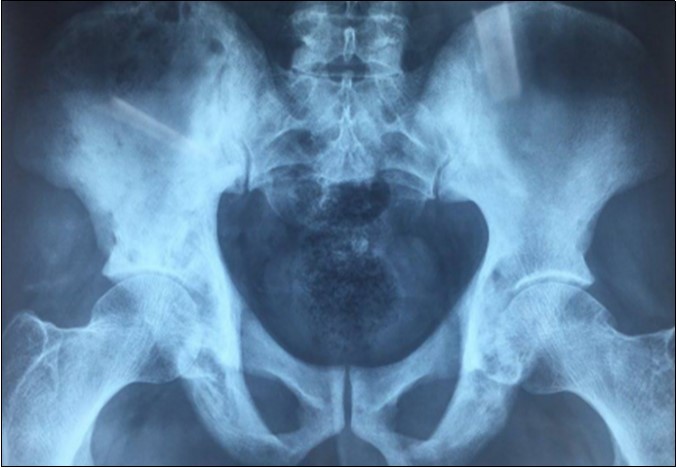

We report the case of an asymptomatic 49 years old male patient, in which a routine check objectified a biological cholestasis (gammagmutamytransferase = 2-3N and ALP = 5-6 N without hyperbilirubinemia or cytolysis). Nos past medical facts were noted. Abdominal ultrasound, viral markers and antibodies measurement (Ac Anti-nuclear, anti-Mitochondrial, anti-LKM1, Anti-cytoplasmic) were normal. Magnetic resonance choalngiopancreatography objectified multiple biliary strictures and parietal irregularities evocative of SC (Figure 1). Colonoscopy showed no associated inflammatory bowel disease. Patient received high doses of ursodeoxycholic acid (20mg/kg) for the SC with partial improvement of liver function but persistence of a marked rise in ALP level. In order to better characterize the nature of ALP, a dosage of ALP isoenzymes was performed and objectified a predominant bone fraction (83%), while liver fractions H1 and H2 were respectively of 12% and 4%. X rays objectified bone condensations with a fibrillar appearance and bone hypertrophy suggestive of PD (Figure 2). A bone scan made for lesions mapping showed a multifocal PD (Figure 3). The patient was treated by bisphosphonates (injections of zoledronic acid), which was associated with a decreasing in ALP level after 6 months.

Figure 2.X ray of the pelvis showing condensations with a fibrillar appearance and hypertrophy of the bone